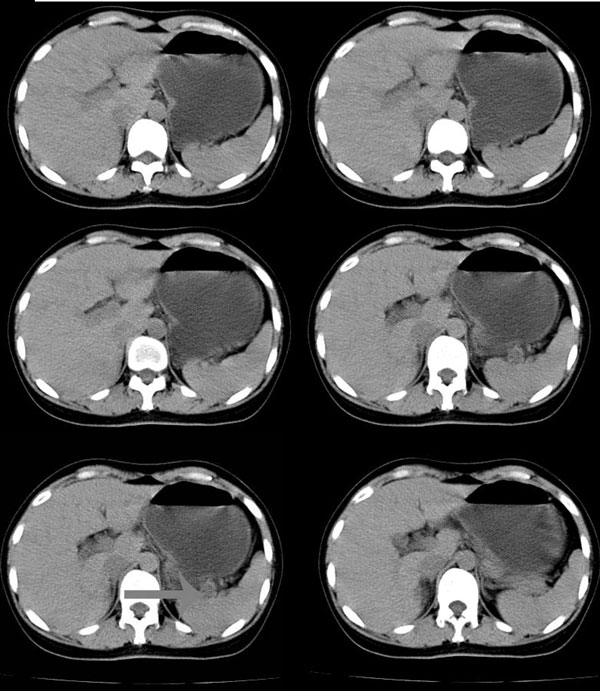

以下是引用无泪之城在2006-11-9 20:01:00的发言:[br]考虑副脾,建议增强,请把增强片传上来

以下是引用guzhongliangddd在2006-11-9 17:55:00的发言:[br]请重点讨论图中箭头所示{脾门部,我首先考虑的是1:血管结构2:胰尾组织??)[br][br][本贴已被 guzhongliangddd 于 2006-11-9 18:01:50 修改过]

以下是引用西北偏北在2006-11-9 20:15:00的发言:[br]箭头所指结构边缘不光整,不支持副脾,考虑胰尾容积层面或血管,做个增强吧.